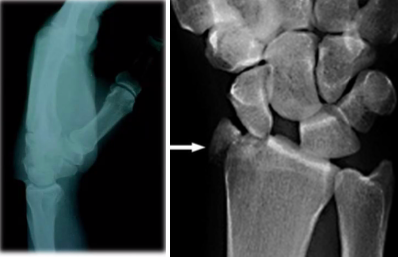

Mecanismo de accion de esta fractura

Fractura del chofer/hutchinson

Compresión del escafoides sobre la apófisis estiloides del radio con la muñeca en dorsiflexión y desviación cubital

Tratamiento de esta fractura

Osteosintesis